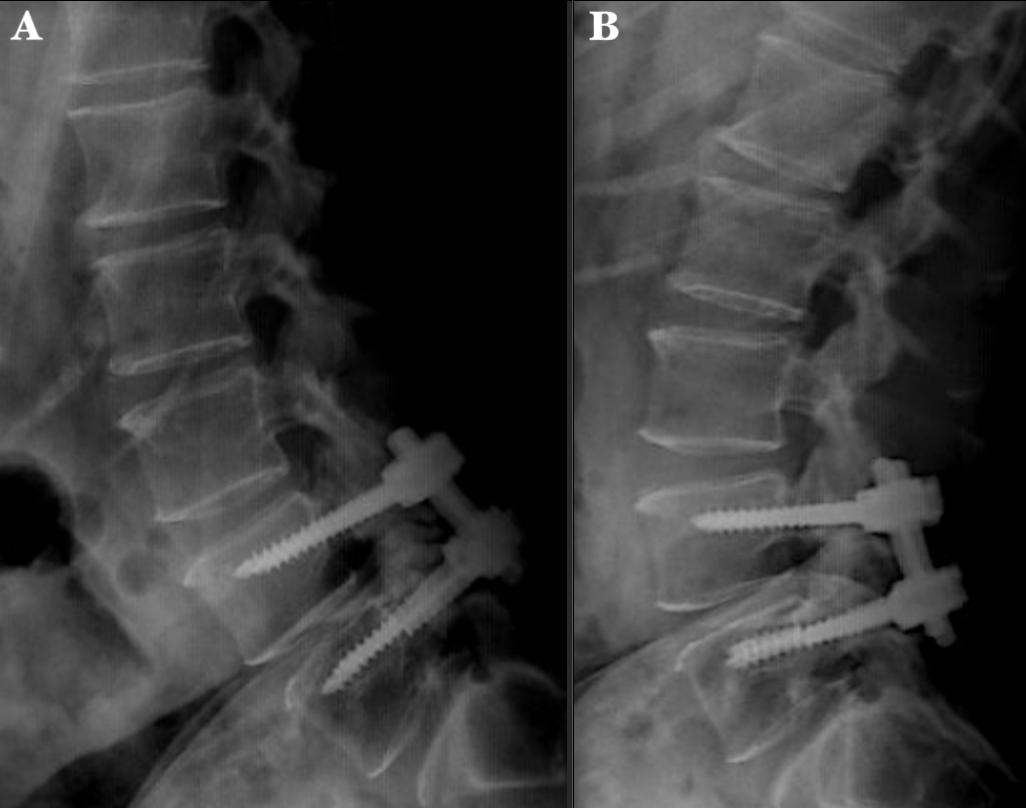

60-year-old male with a history of spondylolisthesis who underwent trough L4-S1 decompression and posterior lumbar instrumentation in 2019. Fourth years postoperative follow - up physical examination revealed a midline surgical scar without abnormalities, mild pain on palpation of the lumbar paravertebral muscles and normal neurologic assessment. Control X-rays were taken showing fatigue of level S1 screws; however, the patient was asymptomatic, therefore, conservative treatment and surveillance were decided, without the need of revision surgery (Figure 4).

Figure 4 X-ray radiographs of the lumbosacral spine. (A) Anteroposterior and (B) lateral radiographs show both S1 screws breakage apparently at the middle level of the length of the threads (6.0x50 mm polyaxial pedicle screws). Interphase is observed at right L4 and L5 screws with no evidence of pull-out..

In case 1, the patient presented progressive pain with VAS 8/10, so we decided to perform the revision surgery considering to bridge the right L5 level, and perform a transforaminal lumbar interbody fusion (TLIF) with posterior fixation (level L3-L4-S1 right and L3-S1 left); it immediately improved stability and pain that occurred with flexion and extension. On the other hand, our case 2 patient has maintained pain control with medication and physiotherapy only, it was demonstrated a definitive radiological failure of the implant, without the need for revision surgery; due to the time passed between the placement of the instrumentation and the follow up, our patient had already presented bone fusion, allowing us to maintain him with a conservative treatment.